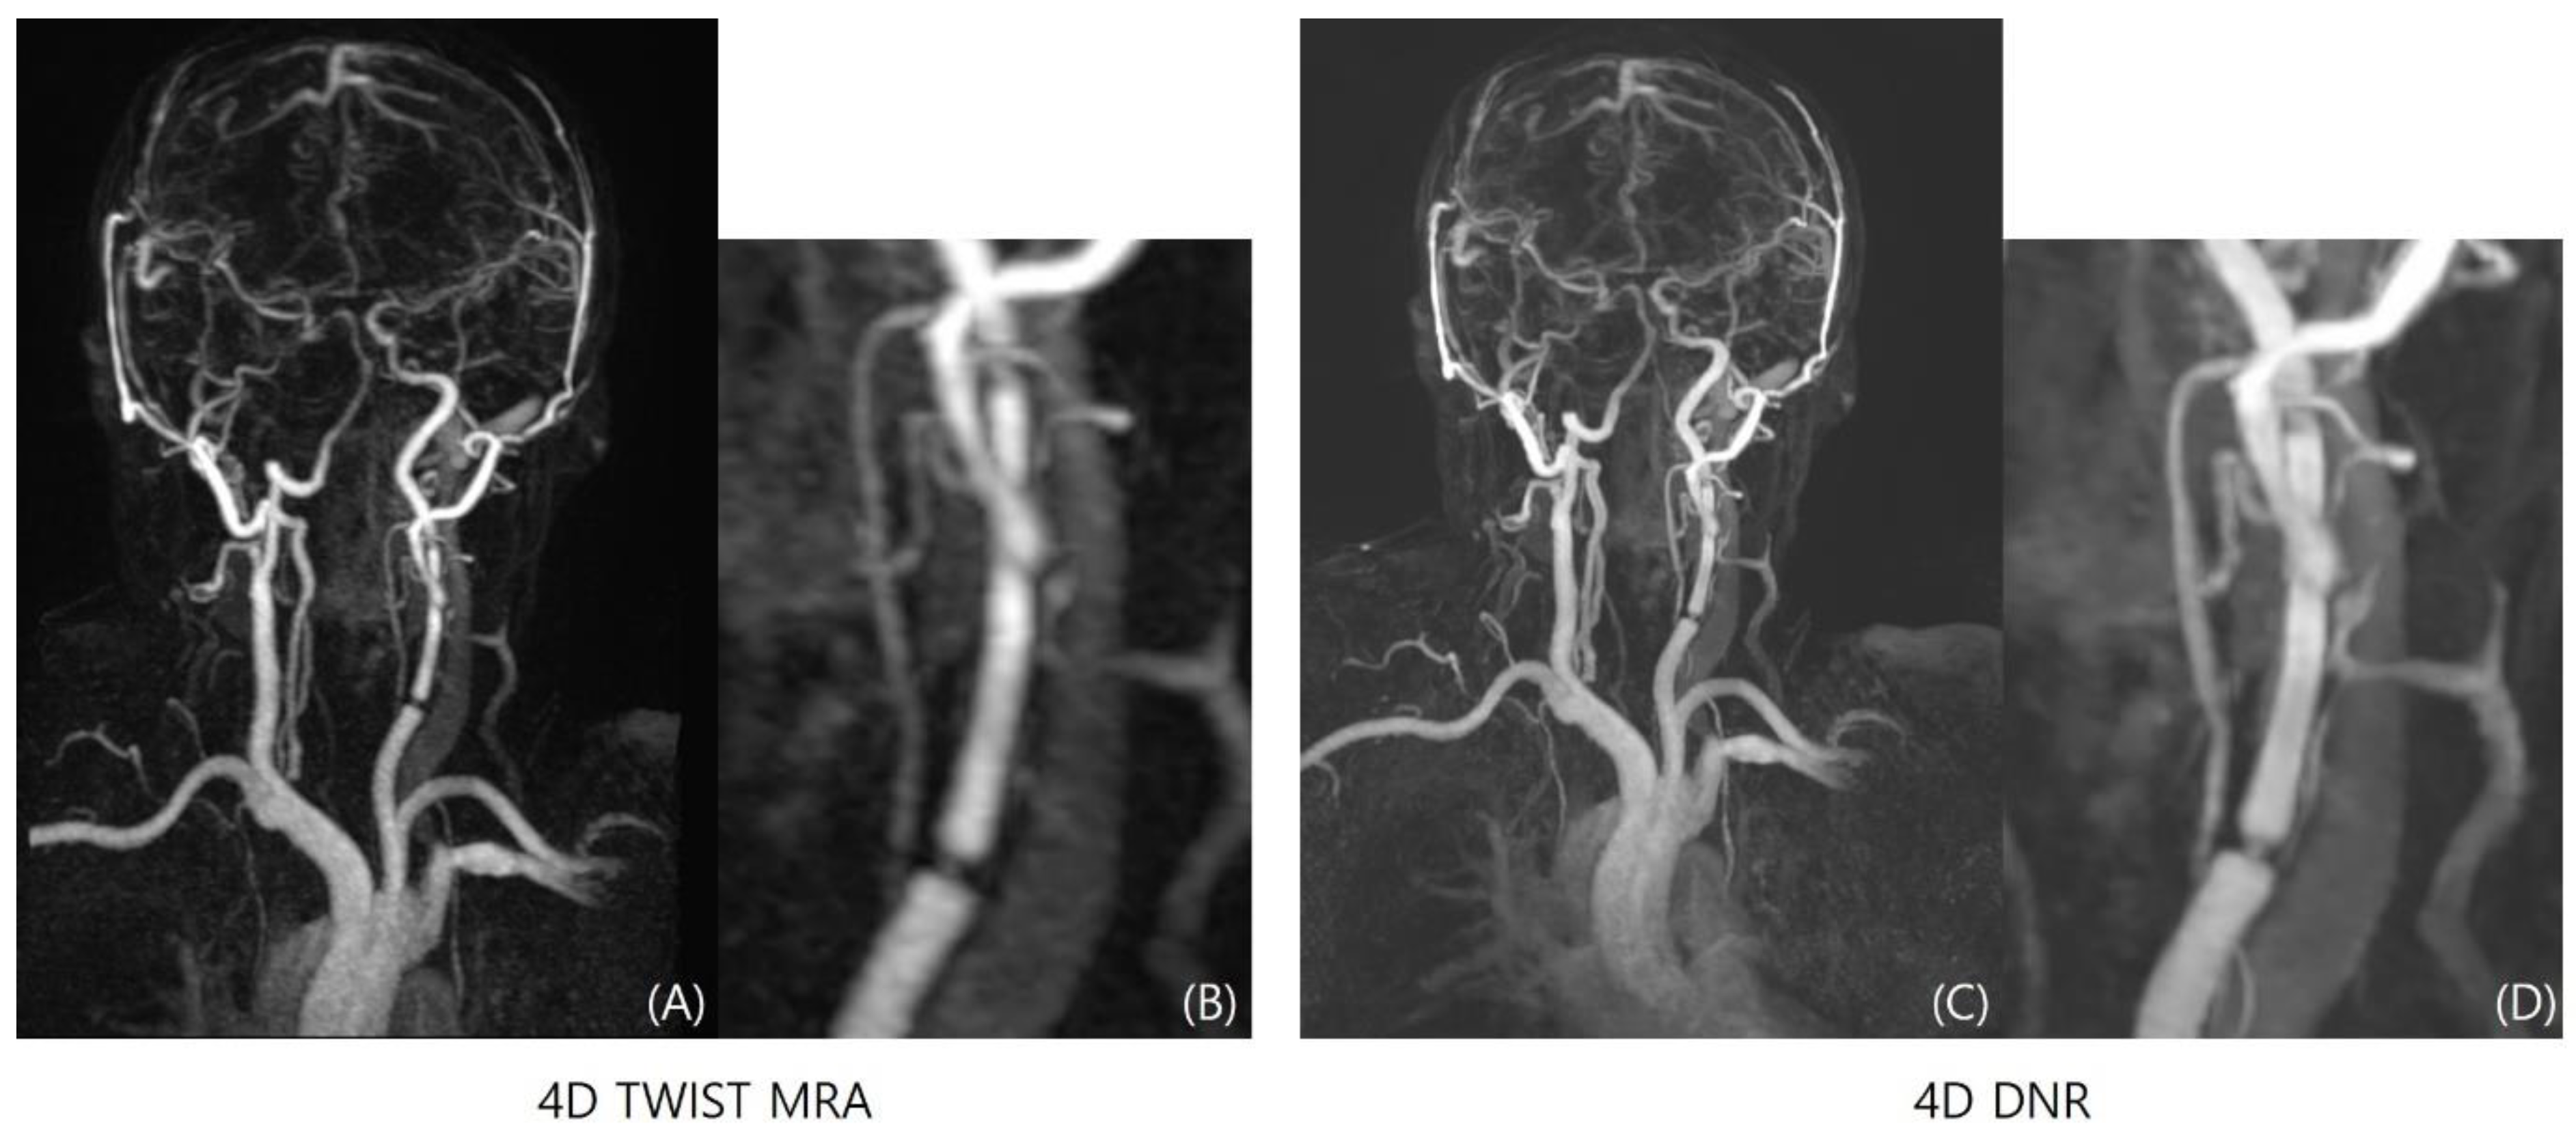

Image Quality Comparison between TOF-MRA, 4D-TWIST-MRA, and 4D-DNR

3.1. Image Quality Assessment

3.3. LVO Evaluation